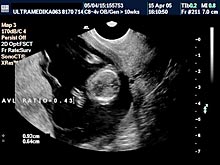

A) Prvi marker za hromozomsku anomaliju (najčešće se misli na trizomiju 21 para hromozoma) je neadekvatna veličina Yolk sac-a (žumančane kese) u 7 nedelji gestacije (GN).

B) Drugi marker je registrovanje postojanje povećane debljine prozračne zone (NT) u vratu ploda-embriona. Obično greške nastaju kada se kontura vrata ploda ne razlikuje od amniona - opne u kojoj se plod nalazi. Osim znanja doktora, rezolucija slike Ultrazvučnog aparata čini ključnu ulogu u merenju ove strukture. Ona-NT se meri u periodu od 9 do 14 GN. Iako je najveća normalna debljina NT 2,5 mm na kraju 14 GN ova vrednost NT može ukazivati na trizomiju ako je registrovana na početku ovog vremenskog perioda. Samo Ultrazvučna kompjuterizovana tomografija može u velikom procentu pouzdano izmeriti ovu strukturu i to na dva načina. Pregled endovaginalnom sondom Braund-band od 8-4MHz, često zbog pozicije ploda nije u stanje da adekvatno registruje NT. Pregled se može znatno zbog toga produžiti i ne mora tačno izmeriti debljinu NT. Međutim u ovakvim situacijama upotrebom Braund-band sondi koje koriste ceo opseg ultrazvučnih talasa od 12 do 5 MHz, pregled se u velikom broju slučajeva završava pregledom preko prednjeg trbušnog zida. Ovaj transabdominalni pregled ima prednosti zbog mogućnosti boljeg pozicioniranja ultrazvučne sonde

u odnosu na položaj ploda, pri čemu je kvalitet slike neuporedivo bolji u odnosu na pregled vaginalnom sondom. Jedino konstitucija trudnice donekle ograničava pregled preko prednjeg trbušnog zida (mokraćna bešika ne mora biti puna).

Povećana debljina NT uz neadekvatnu frekvencu srčanog rada embriona otkriva oko 80 % oštećenih plodova. Važnost ovog ultrazvučnog markera je i u tome što mnoga oštećenja građe ploda takođe bivaju praćena neadekvatnom debljinom vratne regije ploda.